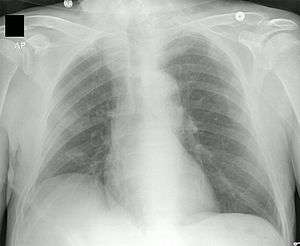

PICCs are usually inserted by physicians, physician assistants (in the US), radiologist assistants (in the US), respiratory therapists, nurse practitioners, or specially trained certified registered nurses and radiologic technologists using ultrasound, chest radiographs, and fluoroscopy to aid in their insertion and to confirm placement. PICC insertion is a sterile procedure, but does not require the use of an operating room. When done at bedside (that is, in the patient's room), a suitable sterile field must be established and maintained throughout the procedure. For this reason, visitors are normally requested to leave the room until the insertion is complete, and some form of skin preparation should be used to clean the patient's skin.